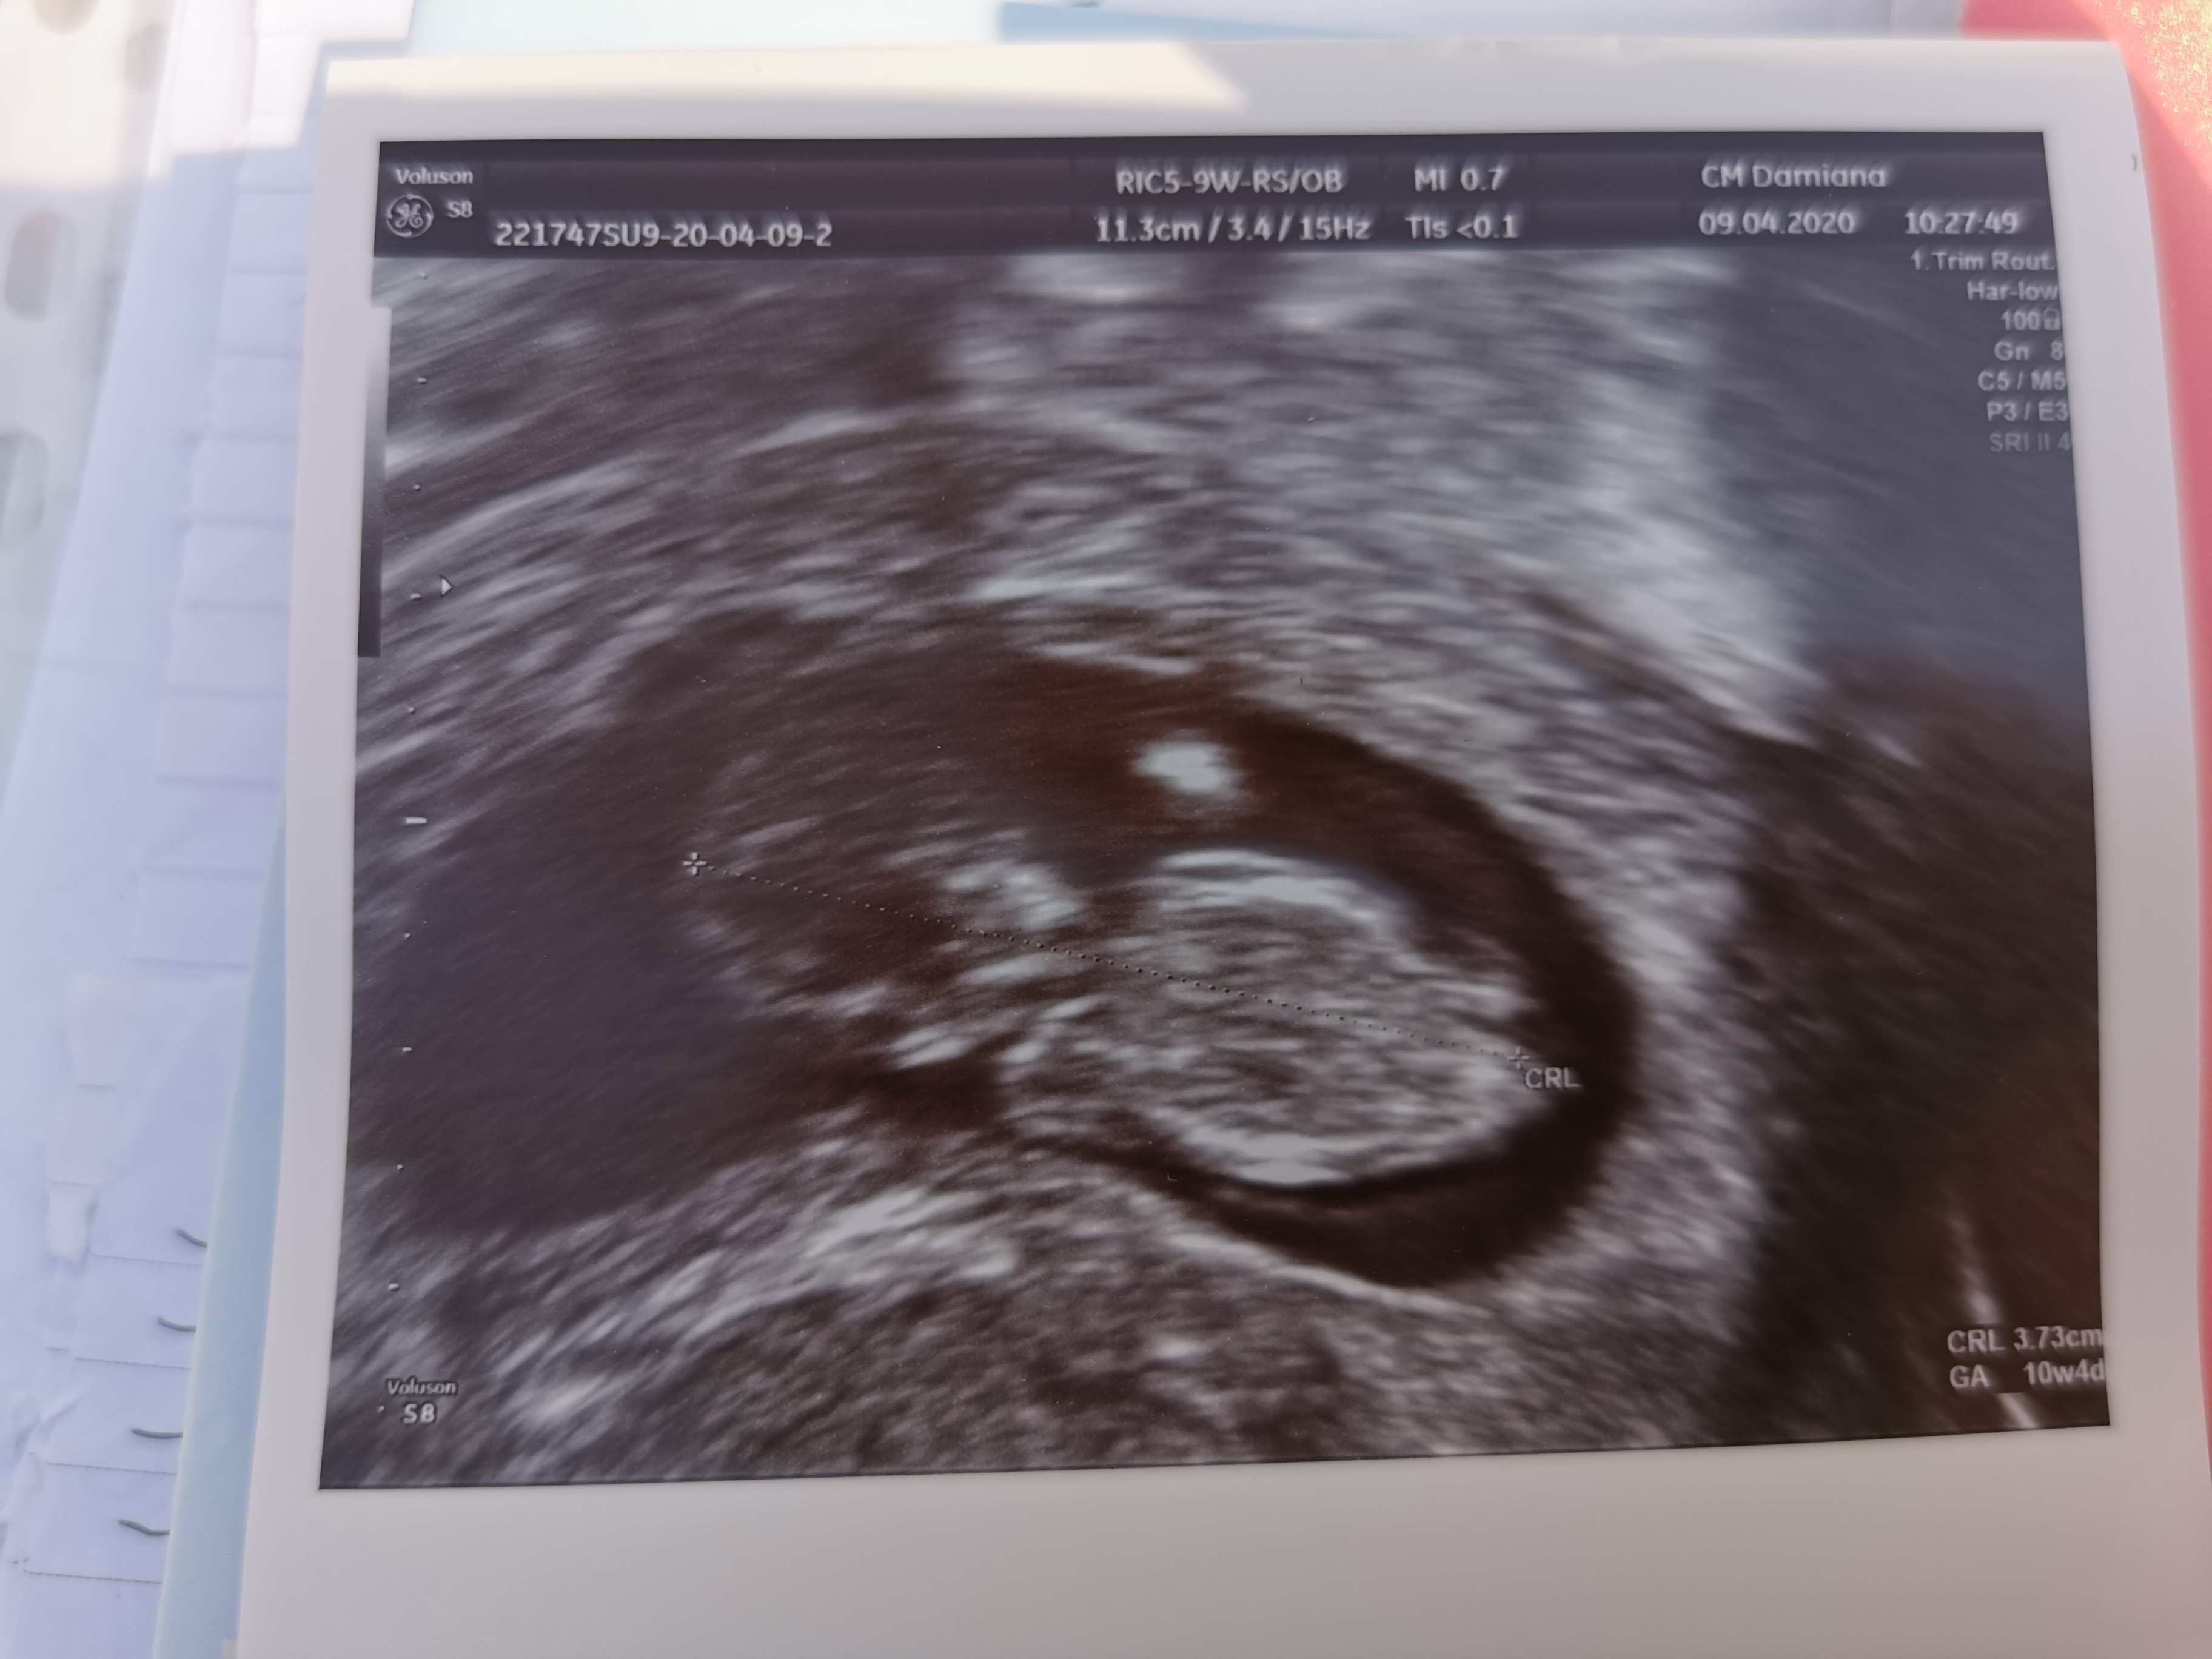

Ja już po wizycie😊U Maleństwa wszystko dobrze❤️❤️❤️rośnie, rusza się 😍, serduszko bije. Ma juz prawie 4cm😊

Na kolejną wizytę w maju mam odpuścić morfologie i mocz, żeby nie chodzić po laboratoriach, skoro wyniki mam przyzwoite. Z usg wyszło mi 10t4d,chciaz z terminu transferu i wieku zarodka powinno być o niecały tydzień wczesniej. Ale whatever😊

Teraz po świętach Nifty, a pod koniec kwietnia Pappa i jak będzie dobrze to może odważę sie powiedzieć babci😊Poznajcie Dziecię 😍To już ewidentnie nie jest Kropek😍